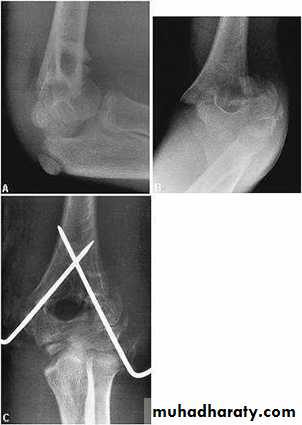

Grade three (completely displaced fract.) :

Manipulation under anesthesia if fail then do close pining or open reduction and fixation by k-wires .

This fracture occur due to fall on out stretched hands . The fracture piece although it look small in the x-ray but it in fact is large and it pulled by extensor muscle of the wrist which attached to it .In sever cases the piece is rotated by the action of the extensor muscle and become capsized lead to nonunion later on if not treated .

If there is no or minimal displacement we can do back slab above the elbow which is 90` flexed and the forearm is neutral ; after 7 days repeat the x-ray for checking and full p.o.p. for 3-4 weeks , followed by active physiotherapy .

Displaced fracture need open reduction and fixation by K-wire or screw